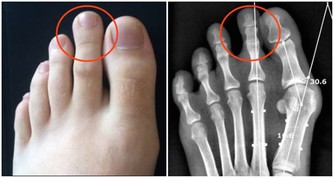

凡屬陰虛火旺、目赤內熱者,或患有癰腫瘡癤、肺炎、肺膿腫、肺結核、胃潰瘍、膽囊炎、腎盂腎炎、糖尿病、痔瘡者,都不宜長期食用生薑。